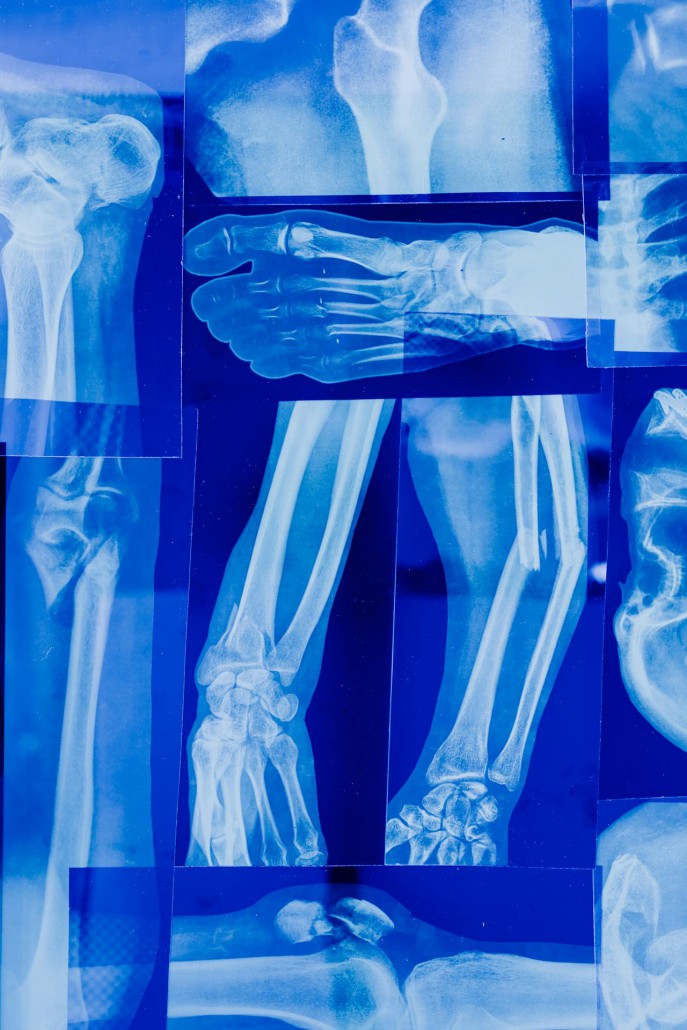

במרבית המקרים צילום רנטגן "רגיל" הוא הבסיס לאבחון, ועל כן הרופא המטפל מספק קודם כל הפניה לבדיקה זו. כך למשל יתבצע צילום רנטגן כשרוצים לראות את המבנה של השלד והשרירים באחת הידיים או אחת הרגליים כשישנו חשש לשבר, או כשידוע שיש שבר ומטרת הבדיקה היא להבין את היקפו ומידת חומרתו. במקרים אלה ייתכן שבמקביל לגפה הפגועה תצולם גם הגפה הבריאה, וזאת כדי שאפשר יהיה להשוות ביניהן. צילומי רנטגן אלה מאפשרים גם אבחון בעיות אורתופדיות נוספות כגון שחיקת מפרקים או מומים מולדים. צילומי רטנגן הם גם כלי מצוין לאבחון פציעות ספורט כגון נקעים, דורבן, תסמונת ITB, שין ספלינט, דלקות בגיד האכילס, דלקת בגידים בכתף, קרע במסובבי הכתף (4 שרירים באזור הכתף) ועוד. האבחון מבוסס על העובדה שכל חומר צפוף (עצם או גידול) סופג את הקרניים ועל כן בצילום הוא נראה בגוון בהיר. עצם שבורה תאפשר לקרינה לעבור דרכה ובצילום יופיע אזור כהה. גם רקמות רכות שהינן צפופות פחות מהנורמה ייראו בצילום כהות.